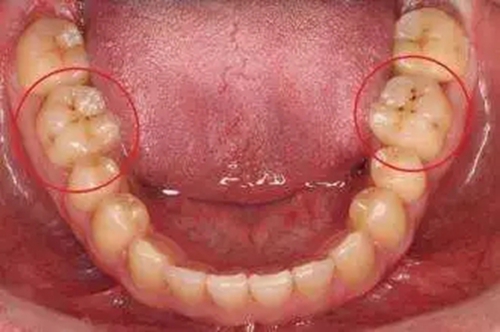

早上刷牙發(fā)現里面的大牙有黑線的情況,一開始我們都會以為可能是食物臟東西殘留在牙齒上,用水漱口就可以清潔掉了。但是,當我們用刷牙清潔、漱口都無法清除黑線的時候,我們就要引起警惕了。因為這種情況下,我們的牙齒已經開始齲蛀了。

1、牙齒表面形成黑線,也就是窩溝齲,這是初步形成的蛀牙。